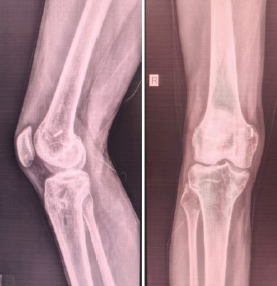

Posterior Cruciate Ligament Rupture in Klippel–Trenaunay Syndrome: Case Report and Review of Literature

Anand Raj Rajendrababu , Varkey Sabu Kulangara , Kiran Ramachandran

………………………………p.126-129